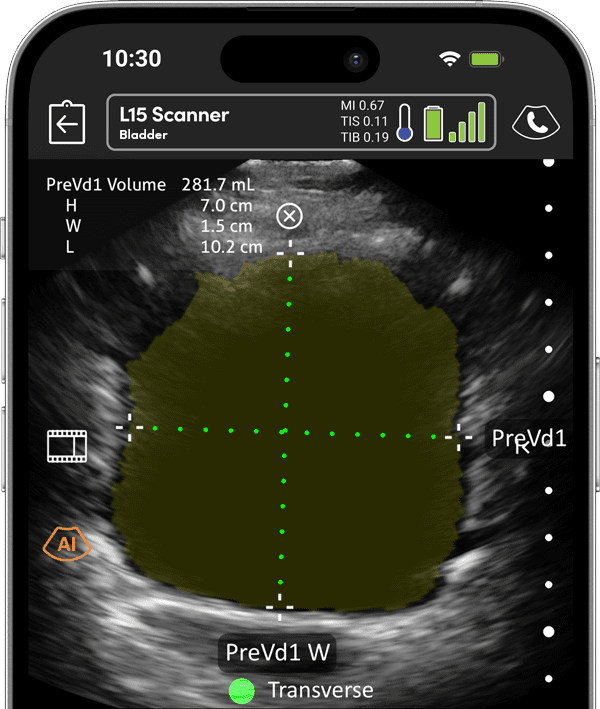

Harness cutting-edge ultrasound technology tailored for Vascular Access